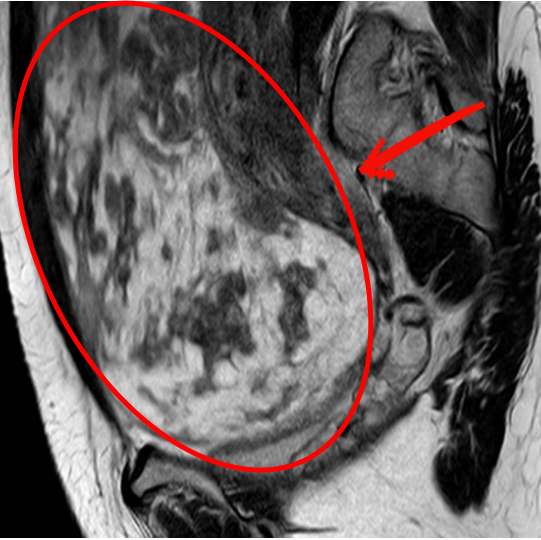

核磁共振进一步确认,这个肿块大小约28×18.58×34.8(厘米3),像冬瓜一样大,边界清晰,上顶横膈膜,下撑骨盆底,没有扩散迹象。

洪女士的核磁共振图像